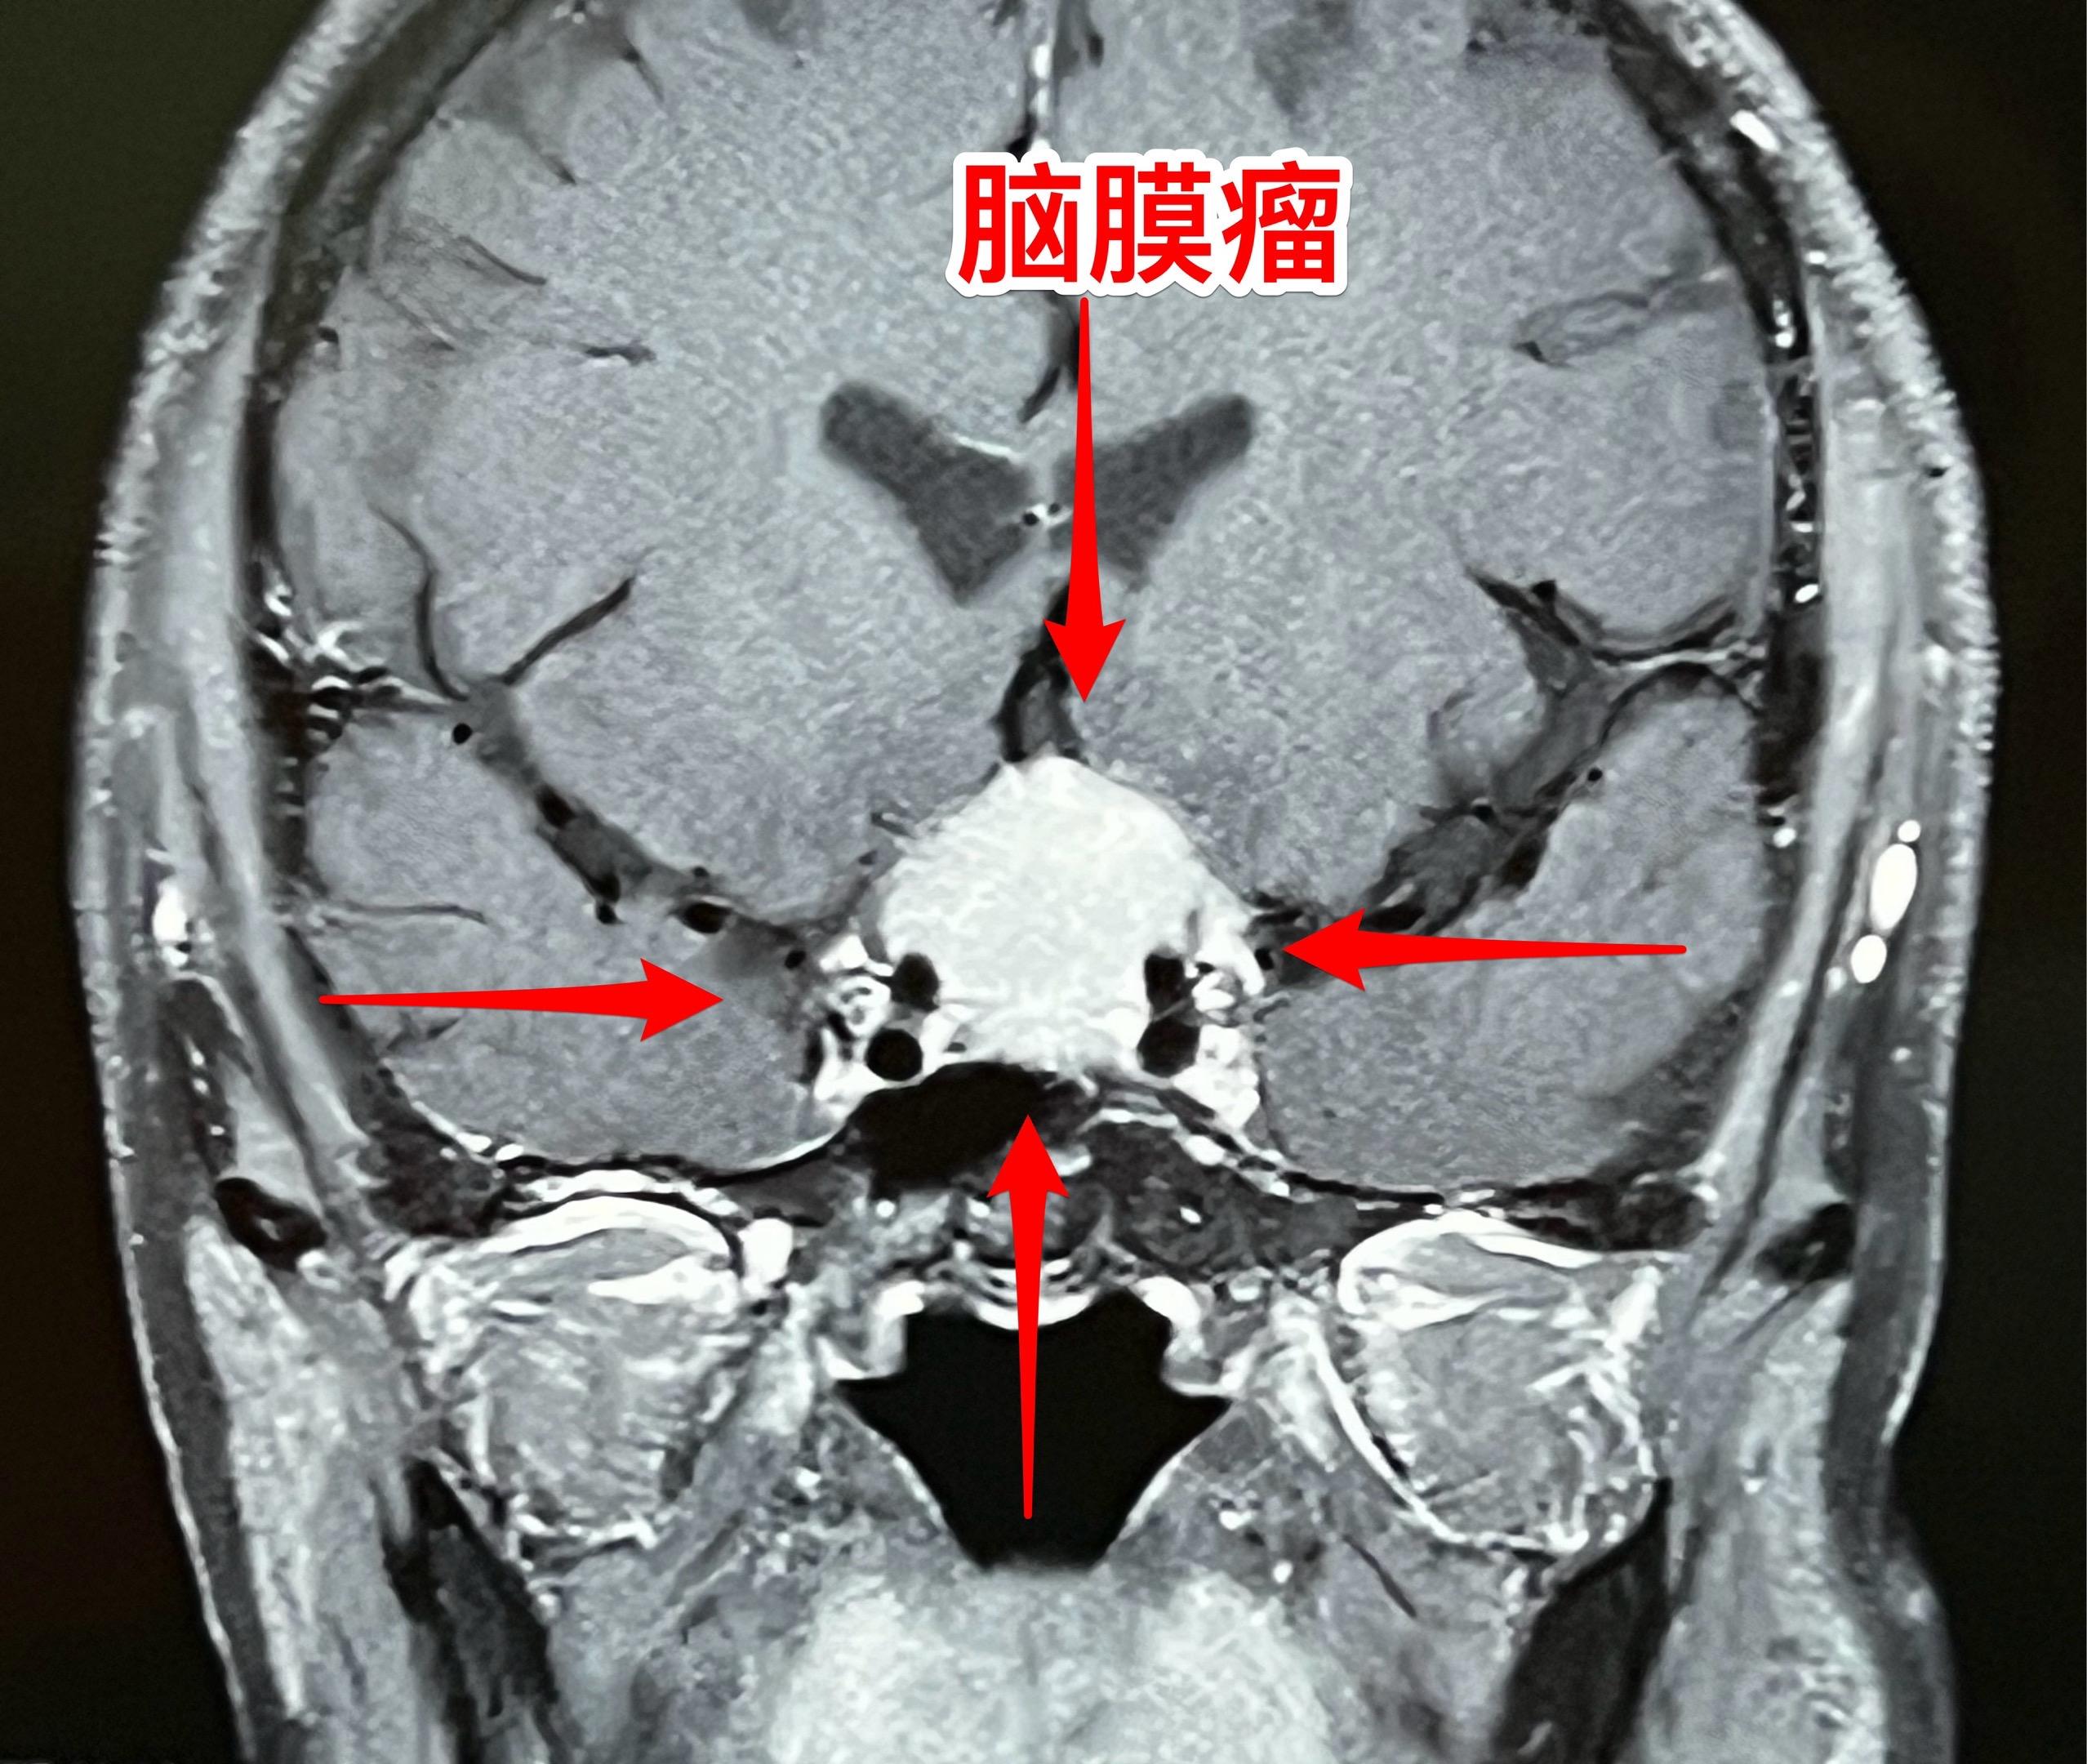

脑膜瘤也会造成视力下降。66岁吉林省女性,退休后喜欢开车到处旅游,并在旅游途中搞直播,拥有三十几万粉丝。 今年她感觉视力明显下降,开车有困难。作了磁共振发现鞍区脑膜瘤,见图。 脑膜瘤属于良性肿瘤,作手术切除肿瘤是最合适的治疗方法。9月16日作了开颅手术,将肿瘤完全切除。手术后病人感视力有改善。脑膜瘤视力下降